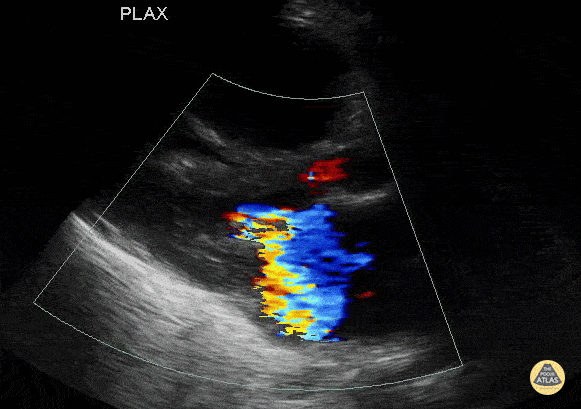

Peds-Cardiac - Multiple valvular abnormalities in a young boy. RV failure.

A 5M stating "my toes hurt." Physical examination shows blue toes. He has a history of congenital sub aortic stenosis with mitral valve regurgitation and stenosis. He was found to have an acute CHF exacerbation with biventricular involvement and mitral stenosis/regurgitation. He was admitted to the PICU on vasopressors. Contributor: John Bowling, DO, Cleveland Clinic Akron General, @BModeBowling